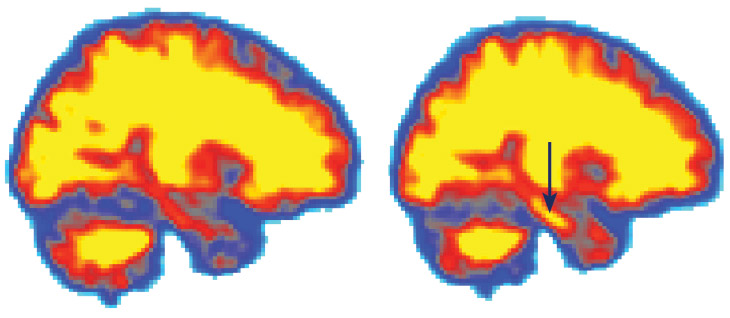

Slumbering stream

Flow of cerebrospinal fluid in a mouse’s brain is much higher during sleep (left, red) than when the animal is awake (right, green).

The day of the experiment, the scientists made a hole in the mice’s skulls, placed a cover over it and injected a dye to measure cerebrospinal fluid in the brain. During sleep, the spaces between the brain cells widened by about 60 percent and allowed more fluid to wash through, taking the metabolic debris, including A-beta, with it.